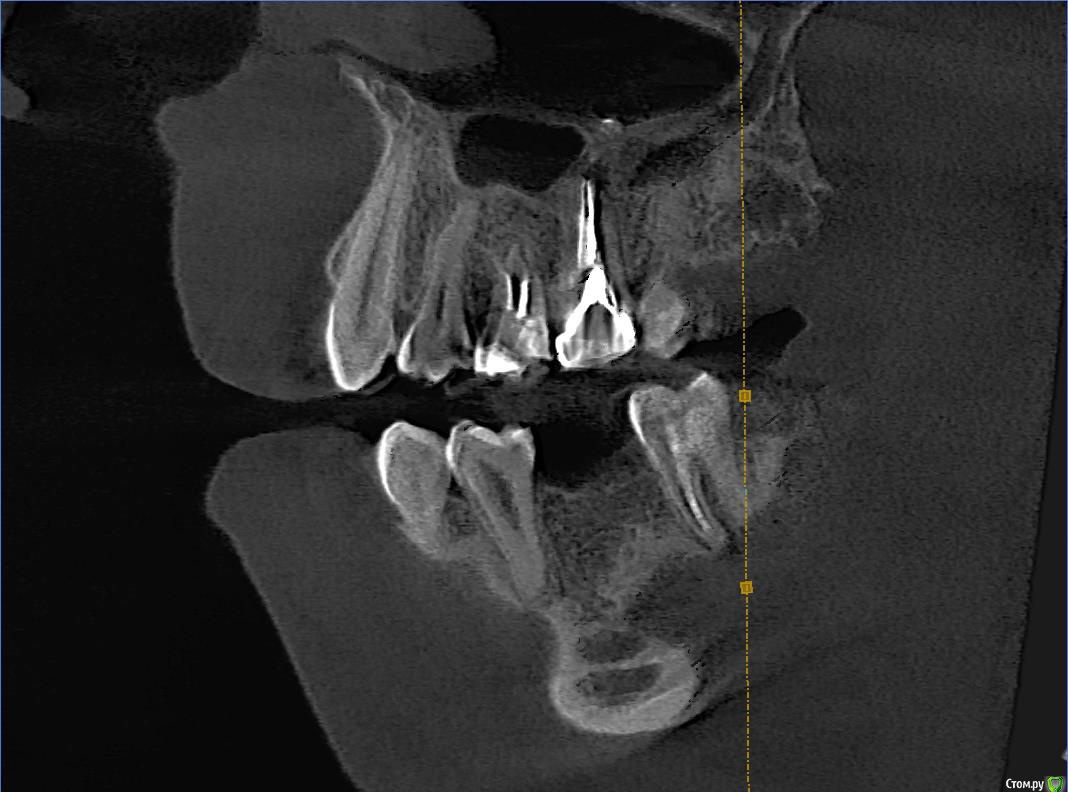

Wolfenstein Опубликовано 12 февраля, 2017 Автор Поделиться Опубликовано 12 февраля, 2017 Снимки прикрепил Ссылка на комментарий

Wolfenstein Опубликовано 12 февраля, 2017 Автор Поделиться Опубликовано 12 февраля, 2017 (изменено) вот еще один снимок Изменено 12 февраля, 2017 пользователем Wolfenstein Ссылка на комментарий

Wolfenstein Опубликовано 13 февраля, 2017 Автор Поделиться Опубликовано 13 февраля, 2017 Теперь вопрос, что стоит удалить? а что оставить? Ссылка на комментарий

Wolfenstein Опубликовано 13 февраля, 2017 Автор Поделиться Опубликовано 13 февраля, 2017 36 Ссылка на комментарий

red_butler Опубликовано 13 февраля, 2017 Поделиться Опубликовано 13 февраля, 2017 363.6 отсутствует, планируйте имплантацию и протезирование Ссылка на комментарий

Wolfenstein Опубликовано 13 февраля, 2017 Автор Поделиться Опубликовано 13 февраля, 2017 3.7 с пломбой Ссылка на комментарий

red_butler Опубликовано 14 февраля, 2017 Поделиться Опубликовано 14 февраля, 2017 что с ним?Да что же из вас жалобы клещами вытягивать приходится...с зубом - периодонтит, требуется повторное эндо лечение и последующее протезирование. Ссылка на комментарий

Wolfenstein Опубликовано 14 февраля, 2017 Автор Поделиться Опубликовано 14 февраля, 2017 Мне сказали, зуб с кистой и требуется удаление, но зуб вроде хороший, и хочется сохранить, думаю возможно ли это? Ссылка на комментарий

Паращук Роман Опубликовано 14 февраля, 2017 Поделиться Опубликовано 14 февраля, 2017 Найдите врача,что понимает толк в "лечении каналов" и с большей вероятностью вас ждет успех. Ссылка на комментарий

red_butler Опубликовано 14 февраля, 2017 Поделиться Опубликовано 14 февраля, 2017 Мне сказали, зуб с кистой и требуется удаление, но зуб вроде хороший, и хочется сохранить, думаю возможно ли это? Удалить успеете, ищите врача и перелечивайте. Ссылка на комментарий

DmitrySH Опубликовано 16 февраля, 2017 Поделиться Опубликовано 16 февраля, 2017 Ну и 24 кариес лечить, 25 ревизия каналов, 26 непонятно что с ним Ссылка на комментарий

Wolfenstein Опубликовано 28 февраля, 2017 Автор Поделиться Опубликовано 28 февраля, 2017 26 - удалил, это вкладка, 27 - нормальный , 28 - нет, он спрятался за деснами, там пусто Ссылка на комментарий